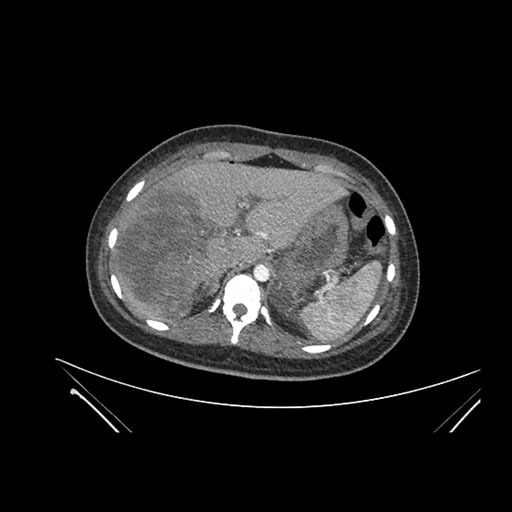

Axial Arterial